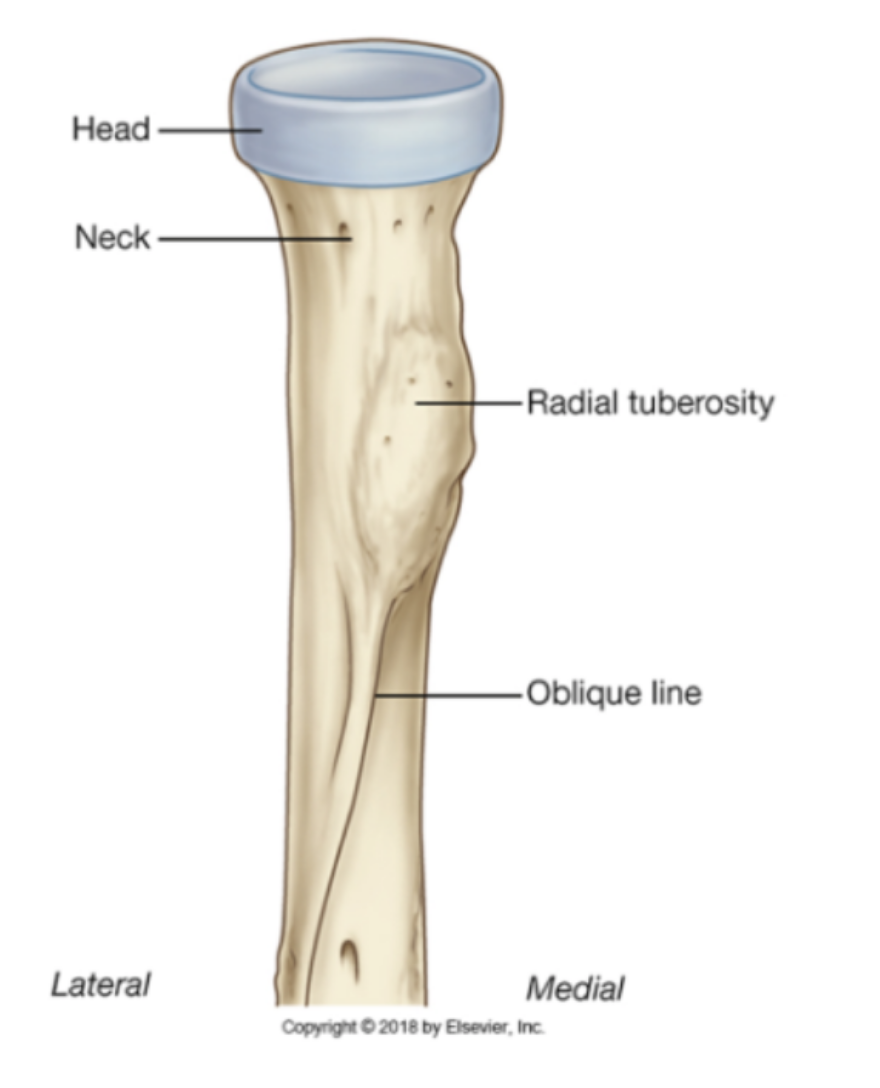

label what you can of the radius

What happens at the radial tuberosity?

insertion of ligaments which support the elbow